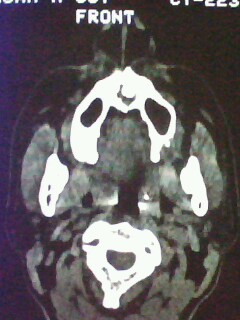

以下是引用随光逐影在2009-5-20 19:22:00的发言:[br]1)考虑左上颌骨近中线区含牙囊肿。2)鼻中隔右突偏曲。3)双侧下鼻甲肥大。